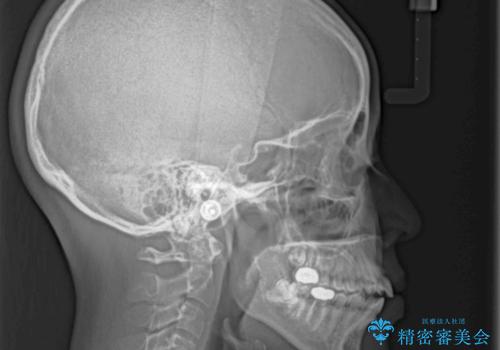

- 唇の閉じにくさを気にして来院された患者様です。

上下左右第一小臼歯4本を抜歯し、ワイヤー装置にて口元を引っ込めるよう矯正治療を行うこととしました。

骨格的に下顎がやや前方にあるため、横顔のシルエットが著しく変化することはありませんでしたが、口元はスッキリと引っ込み、唇が閉じやすくなりました。